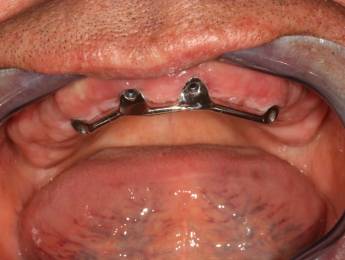

3. eset

4 implantátumra rögzített stéggel stabilizált "Overdenture" megoldás. Költséghatékony módszer fogsorok rögzítésére. Nagyfokú stabilitás érhető el redukált felületeken. Ebben az esetben jól látható, hogy a szájpadlást nem fedi be a kivehető fogsor, az ízlelés is megmarad, mégis javul a rágási képesség és a fogsorok mozgásmentesen rögzülnek.